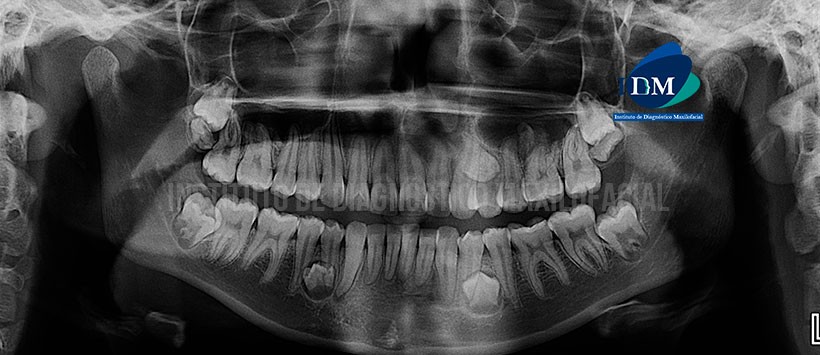

Paciente masculino de 17 años acude al Instituto de Diagnostico maxilofacial para evaluación imagenológica general.

A la evaluación de la radiografía panorámica, evidenciamos que las estructuras presentan una morfología dentro de lo normal, apiñamiento dentario inferior y terceras molares en proceso de erupción. Siendo lo mas resaltante la presencia de múltiples piezas supernumerarias. (Figura 1)